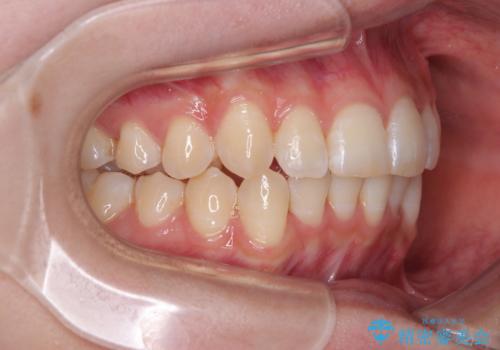

- 上下前歯の重なりを気にして来院された患者様です。

安価なインビザラインパッケージを用いての治療を希望されており、デコボコの程度が中等度であったため、インビザライン・モデレートを用いて矯正治療を行うこととしました。